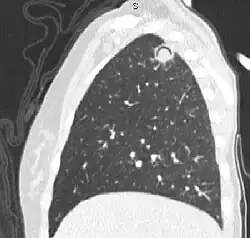

Studio del torace

Storicamente, dopo lo studio dell'encefalo, il torace è il secondo distretto corporeo a essere stato studiato tramite tomografia computerizzata ricavando ottimi risultati, tanto da diventare la metodica diagnostica standard per molte patologie. Infatti, la radiografia del torace, nonostante sia di larghissimo impiego, risulta limitata a causa della sovrapposizione delle strutture anatomiche (problematica solo in parte superabile dall'esecuzione di due proiezioni perpendicolari) che dalla imprecisione su alcune patologie che non permette sempre di ottenere una diagnosi precisa. Inoltre, la risonanza magnetica, per via dei principi fisici alla base del suo funzionamento, poco si presta allo studio dei polmoni caratterizzati dalla presenza di ampi volumi di aria nonché da un continuo movimento (così come per il cuore) per il quale è necessaria una metodica come la TC in grado di scansionare l'intero torace in pochi secondi.[38][39]

L'ampio uso della tomografia computerizzata per lo studio del torace ha portato allo sviluppo di particolari algoritmi di ricostruzione delle immagini, di filtri e di tecniche che permettono di ottimizzare l'esame a seconda dell'organo toracico esaminato e della patologia sospettata. Inoltre, questa metodica risulta fondamentale e praticamente esclusiva per guidare il radiologo interventista nella biopsia di tessuti presenti all'interno della cavità toracica.[40]

Per quanto riguarda i vasi sanguigni, la TC del torace trova larghissimo impegno nello studio dell'arco aortico, in particolare alla ricerca di aneurismi o dissecazioni nonché per la valutazione post-operatoria e nel follow up.[41] Grazie alla TC è inoltre possibile diagnosticare la presenza di una tromboembolia polmonare.[42] Tutti gli esami vascolari richiedono, solitamente, la somministrazione di mezzo di contrasto e spesso sono eseguiti in situazioni di emergenza dove la velocità della metodica risulta essere di fondamentale importanza.[41]

Lo studio del polmone può essere effettuato con grande precisione grazie alla TC per una moltitudine di patologie, al fine sia di giungere a una diagnosi definitiva sia per inquadrare meglio il paziente per successivi indagini. Le ricostruzioni multi-planari possono risultare molto utili nel caso della valutazione di un tumore polmonare o broncopolmonare al fine di conoscere al meglio la sua sede e i rapporti anatomici oltre alla identificazione della dimensione dei linfonodi.[43] Un'acquisizione ad alta risoluzione può essere fondamentale per una corretta valutazione di alcune patologie dell'apparato respiratorio inferiore come, ad esempio, fibrosi polmonare, bronchiettasie, stenosi delle vie respiratore, BPCO, asbestosi, polmoniti, tubercolosi polmonare, ecc.[44]